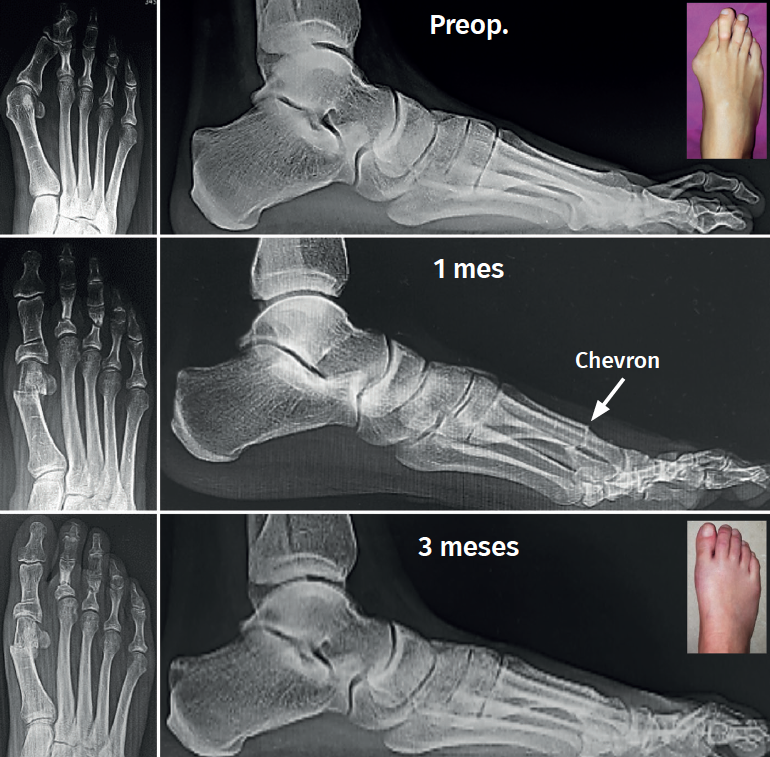

Con respecto a la elevación del metatarsiano, se obtuvo un promedio (DE) preoperatorio de 2,94 mm (0,92). En el postoperatorio al año el promedio (DE) fue de 3,97 mm (0,74). Se observó una diferencia promedio de 1,03 mm de elevación.

Uno de los aspectos importantes en cuanto a la posición de la cabeza metatarsiana es el referente al plano sagital. Pocos trabajos de tratamiento de hallux valgus evalúan el ascenso de la cabeza. En este grupo de pacientes hemos observado que el ascenso de la cabeza es solo de 1,03 mm como promedio y no encontramos en la evolución alguna repercusión clínica asociada con dicho ascenso (Figura 5). Otro aspecto de la osteotomía en Chevron es que históricamente ha sido usada para la corrección de hallux valgus leves a moderados por su ubicación intraarticular, como es la forma clásica abierta o la moderna PeICO(11,12,13). Una de las modificaciones propuestas en este trabajo es hacer la osteotomía PECU a 7 o 10 mm proximal al centro geométrico de la cabeza (ubicación extraarticular), lo que nos permite un mayor desplazamiento y mejora el poder de corrección, asemejándose a una osteotomía diafisaria, como describen autores como Redfern, Vernois, Lee, Hernández, Bauer o Laffenétre en modelos de Chevron percutánea con fijación(3,4,5,9). En este trabajo fueron tratados hallux valgus graves (HV°> 40° e IM° > 16°) de forma satisfactoria.

Las complicaciones asociadas con el Chevron incluyen la necrosis avascular(1,12). En nuestro trabajo no hubo casos y creemos que esto se debe a que, al realizar los gestos de forma percutánea y más proximales, Chevron + abductor + Akin, el daño vascular es menor. Esto también explicaría que las osteotomías tengan un alto porcentaje de consolidación (Figura 6).